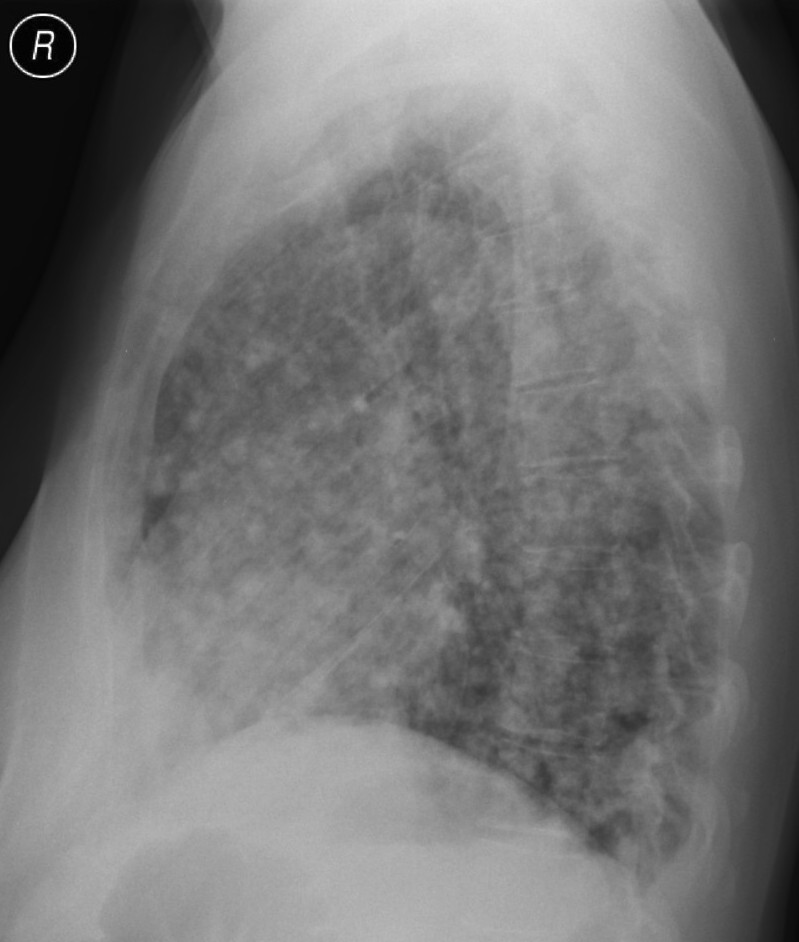

4: Miliary pattern: sarcoidosis, CT, lung window. Axial image and sagittal reformat.

A 67 year old female suffering from COPD. Bilateral rough branching interstitial widening and patchy, miliary nodules with perihilar dominance along the bronchovascular fibres and the fissures.